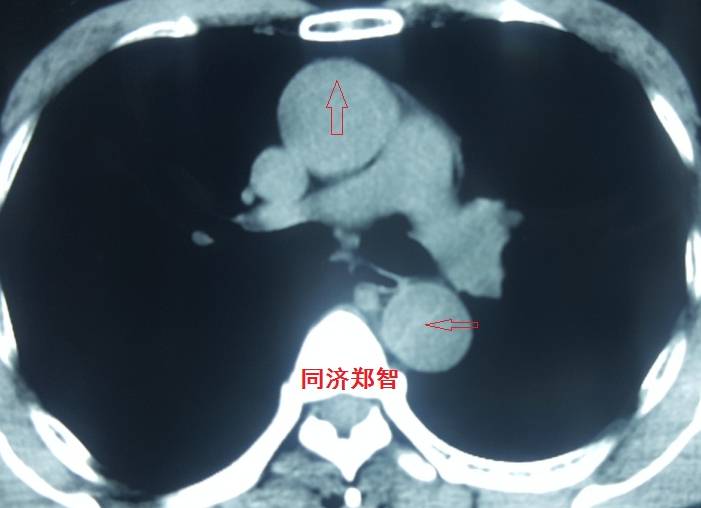

平扫CT提示降主动脉内膜片影(白箭头所示),CTA显示为B型主动脉夹层。

平扫CT提示升主动脉及降主动脉内膜片,CTA证实为A型主动脉壁间血肿。